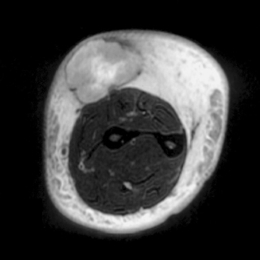

Radiographic imaging is used to help form a diagnosis. These include X-Ray, MRI, CT and Bone Scans

An example of an MRI is shown.